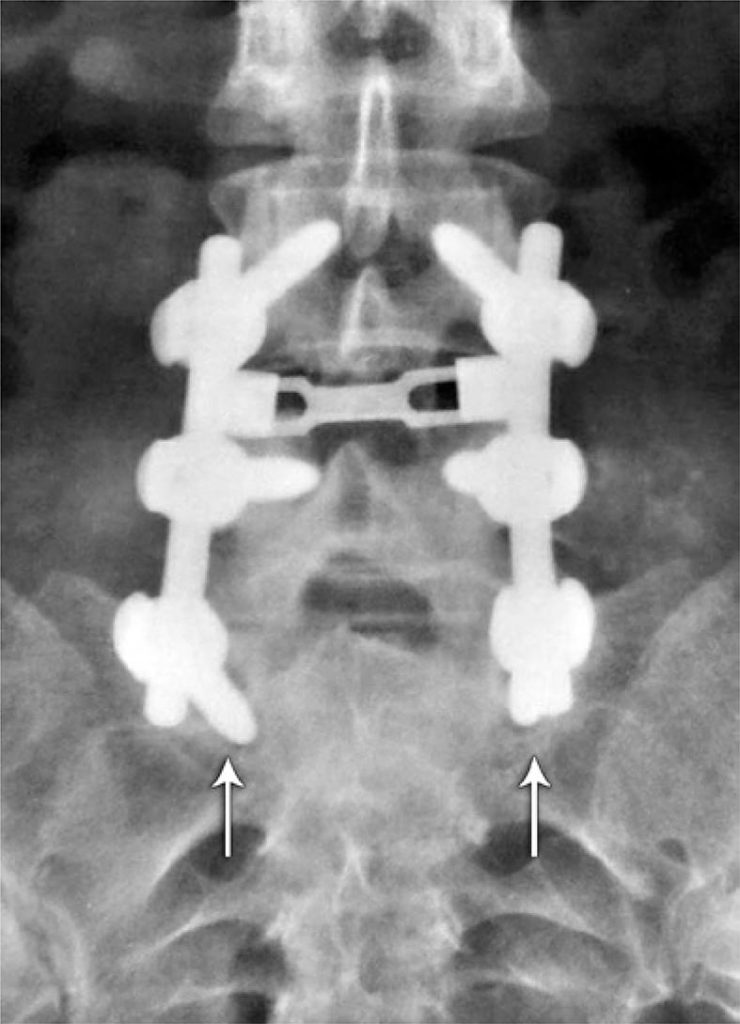

Foram submetidos à fusão posterolateral instrumentada 20 pacientes, avaliados por meio de radiografias anteroposteriores e laterais, em flexão e extensão máximas. As imagens foram avaliadas inicialmente por 6 médicos ortopedistas e, após 8 semanas, reavaliadas por 4 deles, totalizando 400 mensurações radiográficas. Foi realizada análise de confiabilidade intra e interobservador por meio do coeficiente Kappa e pelos critérios de Landis e Koch.

A porcentagem de concordância intra e interobservadores para radiografias anteroposteriores foi, respectivamente, 76 e 63%. Na incidência radiográfica lateral, esses valores foram de 78 e 84%, respectivamente. Entretanto, a análise pelo método de Kappa mostrou concordância fraca e ruim intra e interobservadores para a maior parte dos casos, independentemente do método radiográfico utilizado.

observou-se fraca concordância intra e interobservadores na avaliação da fusão lombossacra por meio de radiografias simples, nas incidências anteroposterior e laterais dinâmicas, não havendo superioridade estatística entre os métodos estudados.